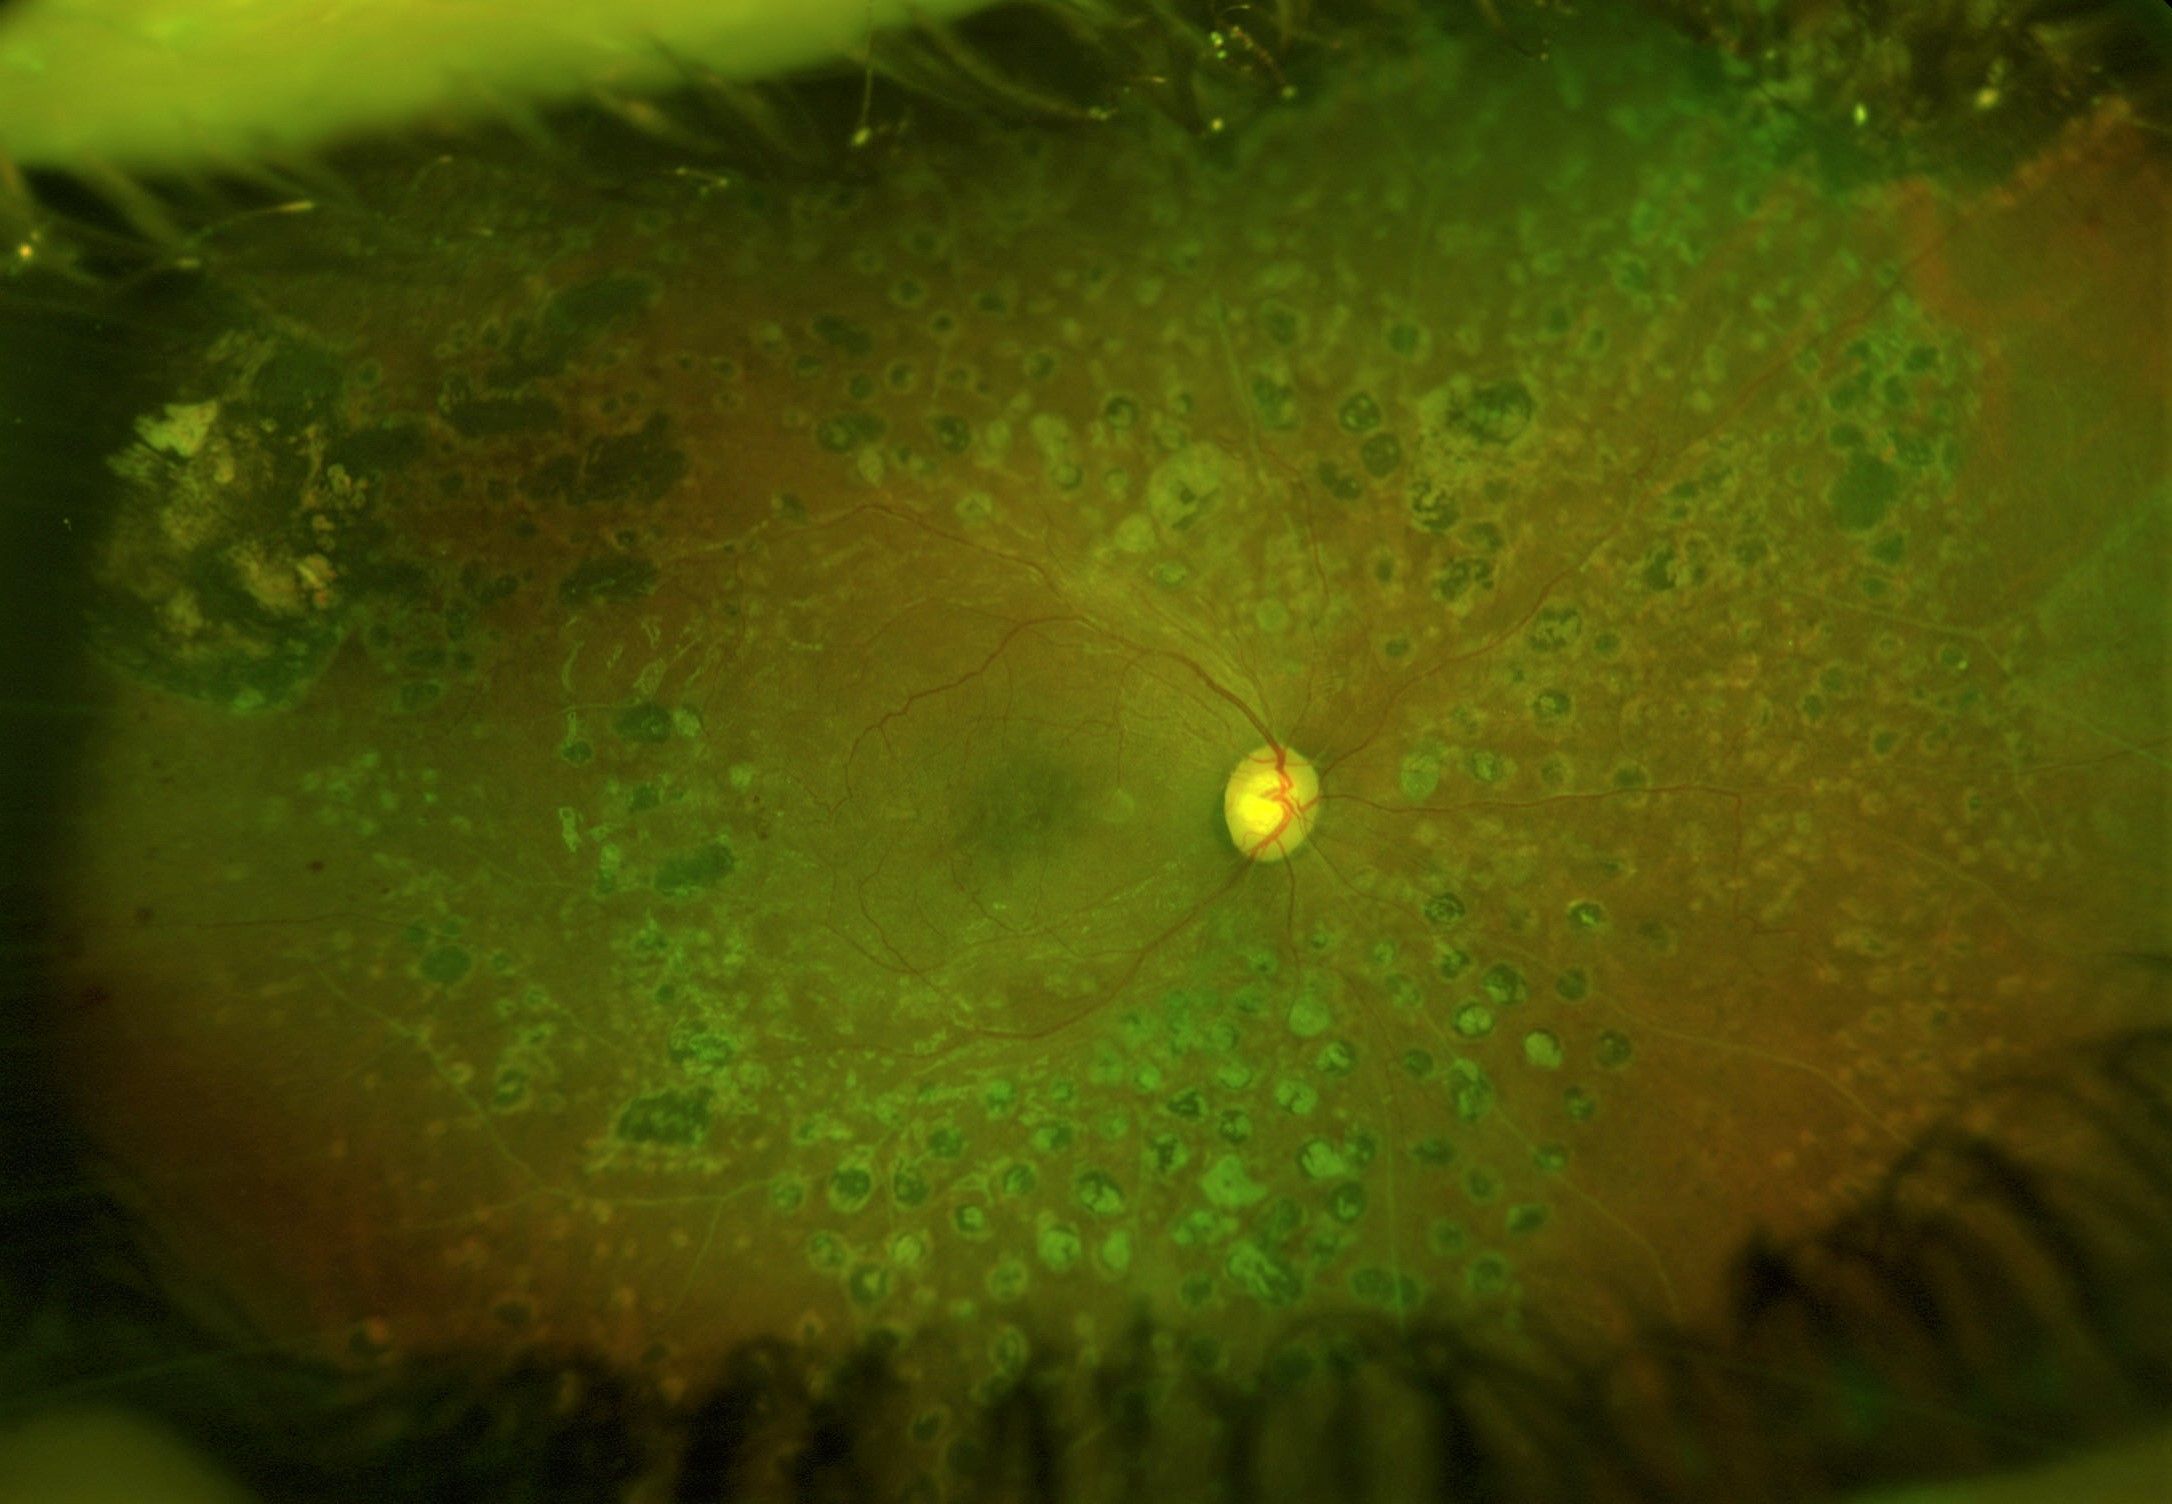

La rétinopathie diabétique

En France, la rétinopathie diabétique RD est la première cause de cécité avant 65 ans.

Le dépistage ophtalmologique d'un patient diabétique est donc essentiel pour sa prise en charge et son suivi.

Identifier les signes d’une RD grâce aux examens cliniques